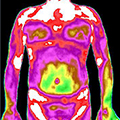

治疗前后炎症对比图/ Inflammation contrast

• 治疗后